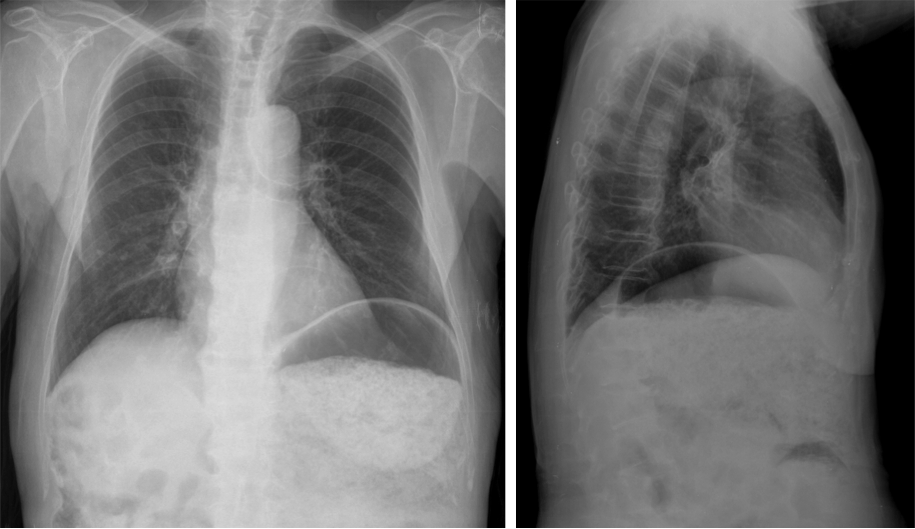

Correlacion con las imagenes anteriores

Correlacion con las imagenes anteriores: en los cortes axial, sagital y coronal puede confirmarse la diltaicón de la cámara gástrica la cual es debido a un litiasis enclavada en primera porción duodenal/píloro gástrico.

Se realiza una TC con contraste en fase portal con cortes de 3 mm y cortes finos para realizar reconstrucciones. Puede realizarse sin contraste para poner aun más de manifiesto la litiasis cálcica. La información obtenida por TC nos permite un diagnóstico rápido y preciso, además de ser una ayuda muy preciada para el cirujano a la hora de decidir el tratamiento a realizar.

Hallazgos:

• Triada de Rigler: obstrucción intestinal + neumobilia +  litiasis ectópica (solo se detecta en el 77% de los casos).

• Dilatación por obstrucción intestinal.

• Distensión de la cámara gástrica.

• Fistulas (normalmente entre vesícula y duodeno)

• Hay que tener cuidado ya que muchas litiasis no están calcificadas y su densidad puede ser similar al contenido del intestino. Pueden ser multiples, por tanto hay que poner atención para que no pasen desapercibidas y evitar las recidivas.